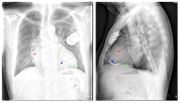

| 19:52, 5 August 2012 | ChestXray.jpg (file) |  |

46 KB | 2 | |

| 20:14, 5 August 2012 | Xthorax.jpg (file) |  |

44 KB | 1 | |